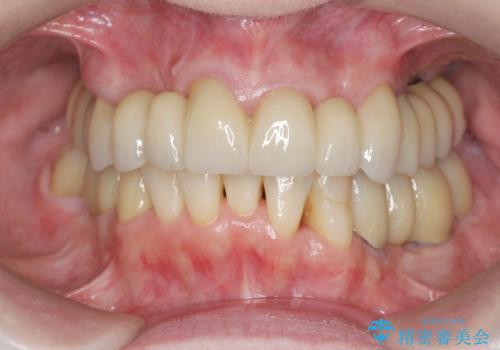

多発した虫歯による咬合崩壊 インプラントを用いた全顎治療

歯の破折・再発した大きな虫歯・根尖病変・歯の欠損、これらの問題を根管治療・歯周外科・インプラント治療・セラミック補綴を行うことで一つづつ解決し安定した咬合状となるよう治療を進めます。

口腔内全体を治療する全顎治療は、期間も長く外科を行う回数も多いためしっかりと通っていただくことが必要不可欠になります。

治療に加えて歯ブラシも上手になることが、治療した歯を長持ちさせるのに必要な要件となります。